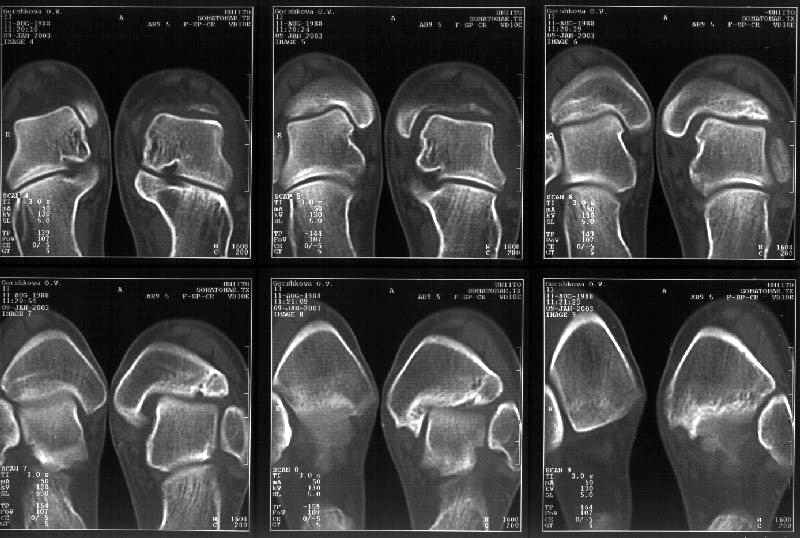

Сегодня пациентке сделали сравнительную КТ. А ксиальные и Фронтальные срезы приложены. Ваше мнение?

Фронтальные

На КТ я попытался изобразить скромными своими способностями (А)- место перелома, (С)- нормальный суставной зазор меж тараном и тремя его маллеолами. (В)- образовавшийся в результате перелома широкий раза в три зазор, позволяющий, по-моему, сублюксацию тарана при ходьбе. В свете данных КТ, критически важных, я бы предложил вертикальную остеотомию места перелома

задне-внутренним подходом и фиксацию мед. маллеола прижатым к тарану с помощью тонкого compression screw. После этого гипсовый сапожок и немедленное расхаживание ноги.